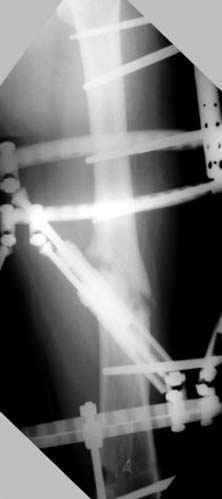

Отправитель: Djoldas Kuldjanov 23 Ноябрь 2004, 18:21

пластическая модель; и коррекция бедра аппаратом Илизарова.

Имею другие снимки тоже, получится как отчет о моей работе.

Отправитель: Evgueny Tschekashkin 24 Ноябрь 2004, 21:09

хотя даже если бы и инфекция , то nail exchange с рассверливанием канала - вариант дебрайдмента) Я думаю, что последовательность развития событий:

Узкий к-м канал - тонкий гвоздь- усталостный перелом дистальных винтов - развитие нестабильности и как ее результат остеолиз вокруг гвоздя - деформация анатомической оси бедра. Похоже, что я понял почему аппарат, а не новый гвоздь:-)